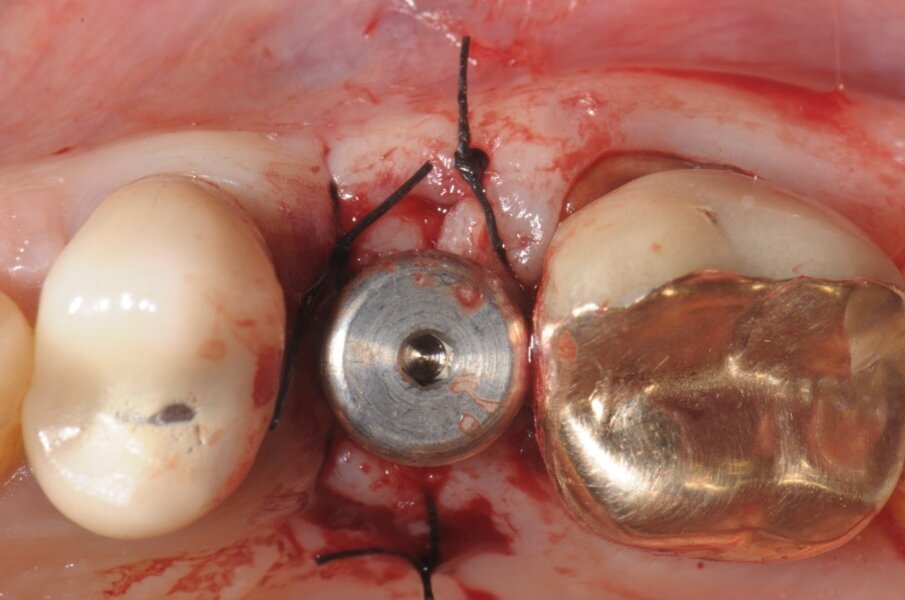

All’ispezione l’alveolo si presentava integro e ben conservato nel perimetro adiacente ai denti limitrofi, la scelta verso l’impianto immediato, nonostante l’evidente mancanza ossea residua oltre apice, che ci avrebbe permesso di ottenere una stabilità primaria apicale è stata comunque svolta grazie a un insieme di fattori concomitanti presenti come: l’uso di un impianto con forma similradicolare con il conseguimento di una stabilità primaria laterale oltre che apicale, pertanto procediamo con il sondaggio di una fresa a diametro crescente sino alla misura voluta che in tal caso era 4.3 mm (Fig. 4). Il taglio verticale delle frese hanno consentito di ottenere un recupero osseo utile per il riempimento di spazi residui. Prima di inserire l’impianto scelto (Conelog 4.3x13 mm-Camlog) procediamo ad ulteriore sondaggio con prova di Valsalva per escludere qualsiasi comunicazione col limitrofo seno mascellare. A procedura ultimata e a impianto inserito, la possibilità è duplice: o chiudere la ferita con un patch mucoso prelevato dal palato4 o posizionare una vite di guarigione sagomata, come nel caso in questione approfittando dello spessore palatino connettivale, prelevare un piccolo patch inserendolo vestibolarmente così da ridurre la morbilità per il paziente stesso e aumentando lo spessore connettivale ai fini estetici (Fig. 5)5.

Fig. 5 - Dopo l’inserimento implantare si procede ad un piccolo prelievo connettivale da posizionare in sede vestibolare, fissato con punti staccati di sutura acrilica in Nylon 5/0.